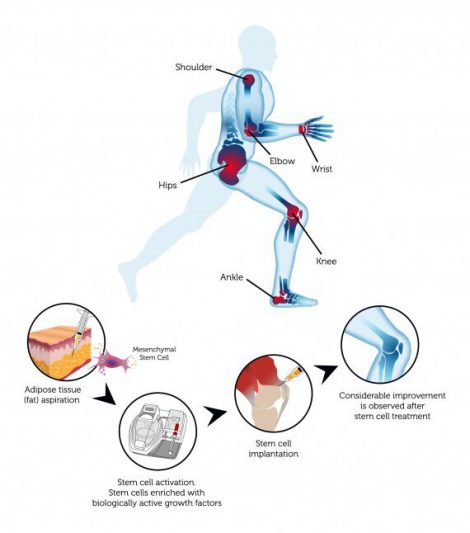

ดังนั้น การรักษาอาการบาดเจ็บที่เกิดจากการเล่นกีฬาด้วยเซลล์ต้นกำเนิดที่สกัดมาจากไขมันจะให้ผลลัพธ์จากการรักษาอย่างมีประสิทธิภาพเนื่องจากเซลล์ต้นกำเนิดที่สกัดไขมันมีส่วนประกอบของGrowth Factors และมีคุณลักษณะในการเป็นสารต้านการอักเสบ ซึ่งวิธีรักษานี้จะให้ผลลัพธ์ที่ดีมากยิ่งขึ้นเมื่อใช้กับผู้ที่มีอาการบาดเจ็บเกิดขึ้นเป็นระยะเวลานานหลายสัปดาห์หรือหลายเดือน

อาการบาดเจ็บที่เกิดจากการเล่นกีฬานั้นสามารถบรรเทาได้ด้วยการใช้ adult stem cells ซึ่งการเล่นกีฬานั้นสามารถจำแนกได้ออกเป็นหลายชนิด ซึ่งแต่ละชนิดจะมีวิธีการรักษาและผลลัพธ์จากการรักษาที่แตกต่างกันออกไป

A: สเต็มเซลล์เป็นเซลล์ต้นกำเนิดที่มีลักษณะพิเศษในร่างกายของเรา โดยเซลล์ต้นกำเนิดนั้นมีคุณสมบัติที่สำคัญสองประการ ได้แก่ เซลล์ต้นกำเนิดสามารถทำสำเนาตัวเองใหม่ และด้วยคุณสมบัตินี้เซลล์ต้นกำเนิดเพียงหนึ่งเซลล์จึงสามารถแตกตัวเองออกมาได้อย่างไม่มีที่สิ้นสุด

คุณสมบัติอีกประการ คือ คุณสมบัติในการพัฒนากลายเป็นเซลล์ชนิดอื่น เช่น เซลล์ต้นกำเนิดที่สกัดจากเซลล์ไขมันในห้องปฏิบัติ สามารถพัฒนาตัวเองกลายไปเป็นเนื้อเยื่อกระดูกอ่อนเพื่อสร้างกล้ามเนื้อกระดูกอ่อน หรือกลายไปเป็นเซลล์ประเภทอื่น ๆ อย่างเซลล์ผิวหนังหรือเซลล์กระดูก ในทางทฤษฎีแล้ว

คุณสมบัตินี้สามารถทำให้เซลล์ต้นกำเนิดเกิดการพัฒนาและกลายสภาพไปเป็นเซลล์ประเภทอื่นเพื่อซ่อมแซมได้อย่างไม่มีที่สิ้นสุดเช่นกัน

เซลล์ต้นกำเนิดนั้นสามารถสกัดได้จากแหล่งต่าง ๆ เช่น ตัวอ่อน (embryos) เลือดที่ได้จากสายสะดือ (umbilical cord blood) และเซลล์ของผู้ใหญ่ (adult stem cells) สำหรับ adult stemcells นั้นจะสกัดมาจากผู้ใหญ่แต่เพียงอย่างเดียว ซึ่งเซลล์ต้นกำเนิดที่โตเต็มวัยนั้นจะมีประสิทธิภาพในการพัฒนาเปลี่ยนแปลงตัวเองกลายเป็นเซลล์ชนิดอื่น ๆ

adult stem cells สามารถสกัดมาได้จาก 2 แหล่งใหญ่ๆ คือได้แก่ เซลล์ไขมัน และไขกระดูก

ส่วนที่สกัดจากแหล่งไขมันจะมีชื่อเรียกว่า adipose-derived adult stem cell ซึ่งจะเป็นเซลล์ต้นกำเนิดที่ง่ายต่อการสกัดและมีจำนวนอุดมสมบรูณ์อย่างมากเมื่อเทียบกับแหล่งชนิดอื่น ๆ

A: การให้การรักษาด้วยสเต็มเซลล์นั้นส่วนใหญ่แล้วจะใช้วิธีส่งสเต็มเซลล์เข้าไปในบริเวณที่ได้รับบาดเจ็บด้วยการปลูกถ่ายโดยการฉีดเข้าเส้นเลือดดำ (intravenous) หรือ IV และจากการดำเนินการทดสอบพบว่าการใช้วิธีดังกล่าวนั้นเพิ่มประสิทธิภาพในการรักษาและให้ผลลัพธ์การรักษาที่ดีมากยิ่งขึ้น